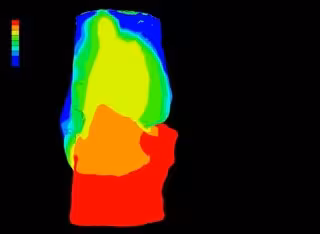

Para ello, los científicos han realizado una comparación de diferentes métodos para asignar las propiedades mecánicas y así tener un modelo predictivo de la rigidez que adquiere el nuevo hueso. Por un lado, a través de la Tomografía Axial Computarizada (TAC), la observación del nivel de gris que aparece en la imagen, se ha asociado a diversas propiedades que tiene el material. Otro método está basado en pruebas de laboratorio de los callos formados a través de técnicas nanométricas.

El estudio titulado 'Comparison of methods for assigning the material properties of the distraction callus in computational models', publicado en la revista International Journal for Numerical Methods in Biomedical Engineering, realiza la combinación de métodos que supone un perfeccionamiento de la predicción, teniendo en cuenta principalmente los dos primeros métodos utilizados, ya que los resultados relativos a la rigidez eran parecidos.